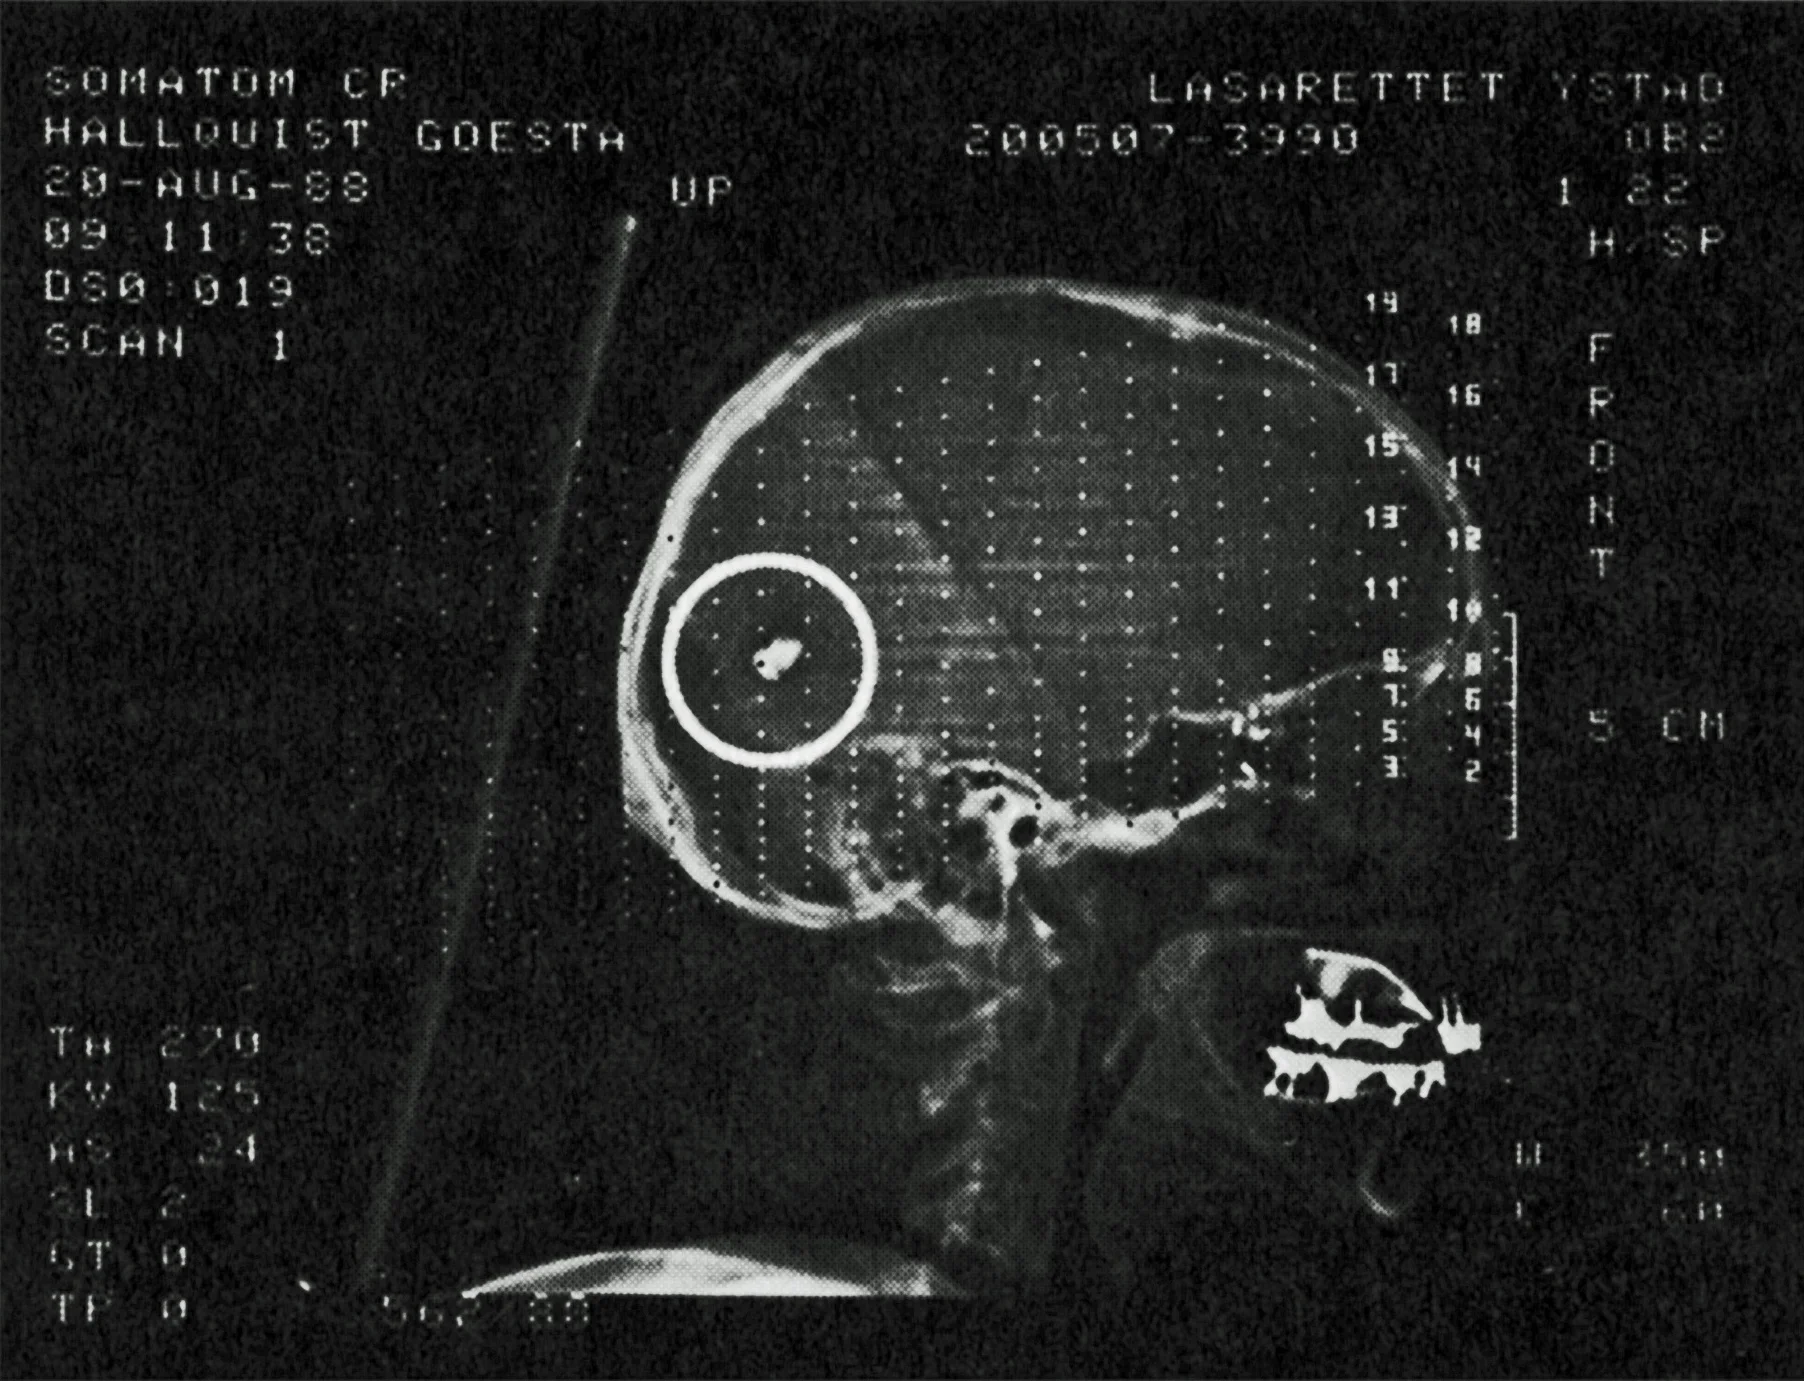

Bild från Löjtnant Hallquists dagbok. “På det här röntgenfotot från 1998 ser man tydligt kulan i bakre delen av huvudet. Dessutom sitter två splitter i vänstra tinningen.”